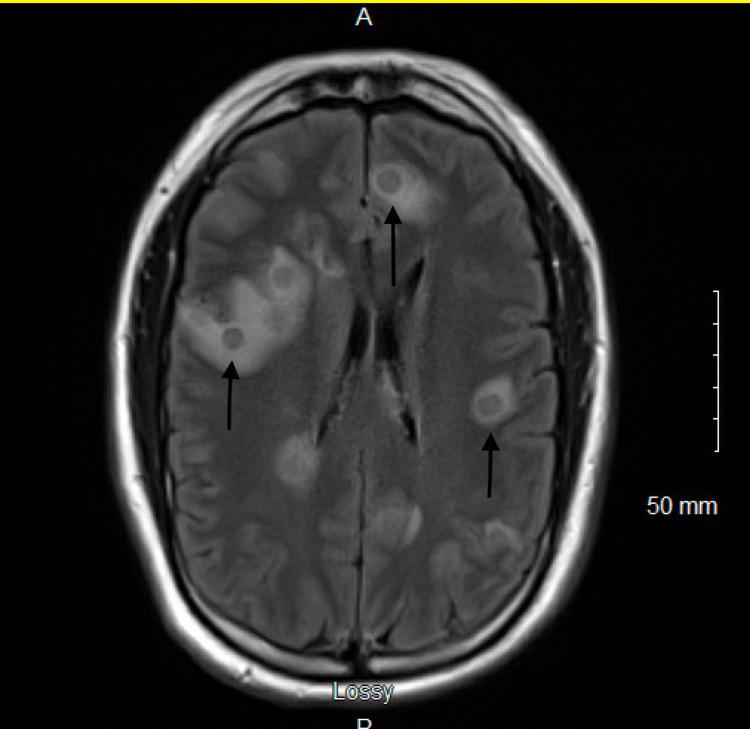

中间型链球菌所致多灶性脑脓肿

Multifocal Brain Abscesses Due to Streptococcus intermedius.

Brain abscess is a life-threatening illness that occurs when an intracerebral infection leads to cerebritis and subsequent pus formation within a well-vascularized capsule. While streptococci (aerobic, anaerobic, and microaerophilic) are the most common bacteria isolated, its presentation as multifocal brain abscesses is rarely described. In this report, we describe a 43-year-old male patient who presented to the emergency department due to progressive lethargy and low-grade fever of seven days worsening. Upon further evaluation, the patient was found to have multiple brain abscesses secondary to confirmed by the culture of stereotactic aspiration of brain collection. This case underlines the importance of considering as a cause of multifocal brain abscesses.

摘要

脑脓肿是一种危及生命的疾病,当脑内感染导致脑炎并随后在血管丰富的包膜内形成脓液时就会发生。虽然链球菌(需氧菌、厌氧菌和微需氧菌)是最常分离出的细菌,但其表现为多灶性脑脓肿的情况很少被描述。在本报告中,我们描述了一名43岁男性患者,他因进行性嗜睡和持续7天加重的低热而到急诊科就诊。经过进一步评估,通过对脑采集物进行立体定向抽吸培养确诊,该患者继发于[此处原文缺失相关内容]的多个脑脓肿。本病例强调了将[此处原文缺失相关内容]视为多灶性脑脓肿病因的重要性。